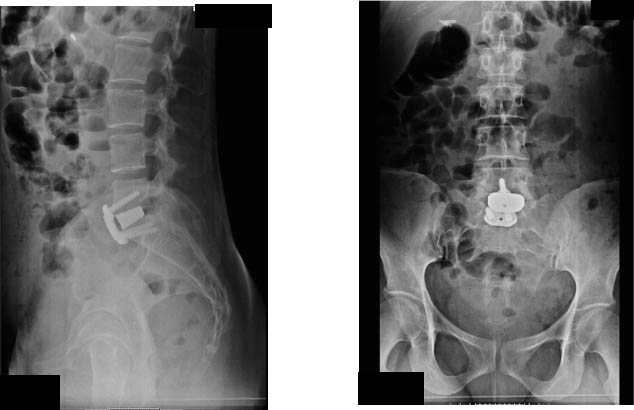

Cura Dolore Lombare Vergiate Varese

Cura Dolore Lombare La discopatia degenerativa è una delle cause più frequenti di lombalgia cronica associata spesso a irradiazione del dolore lungo gli arti inferiori. L’80% delle persone ha sperimentato nella vita il dolore lombare. [huge_it_gallery id="3"]   Principale sintomo è il Dolore lombare resistente alle terapie con o senza irradiazioni agli arti inferiori. Non esiste…